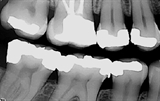

røntgenbilde av tenner

Røntgenbilder viser blant annet begynnende hull, behandlingskrevende hull, gamle fyllinger og tennenes benfeste.

Det finnes forskjellige former for røntgenbilder. Ved en regelmessig undersøkelse er det vanligvis såkalte bitewings som benyttes. Bitewings gir tannlegen informasjon om blant annet hull i tennene, begynnende hull og kvaliteten til gamle fyllinger. De kan også si noe om tennenes feste og avdekke tegn til periodontitt (tannløsningssykdom). Ved behov kan bitewingbildene måtte suppleres med andre småbilder (for eksempel rotbilder) av avgrensede områder.